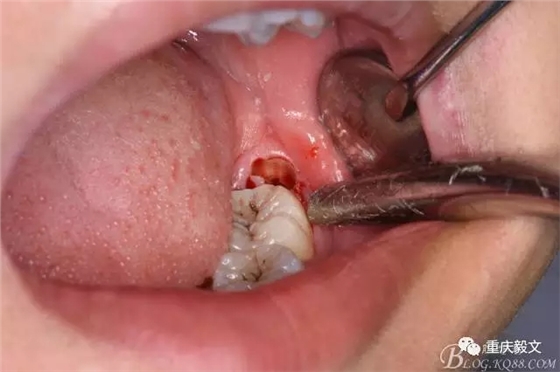

圖2.口內(nèi)可見黃豆大小大遠(yuǎn)中面暴露,擬采用潛掘法分牙,分別取出牙冠、牙根,達(dá)到真正的微創(chuàng)拔牙